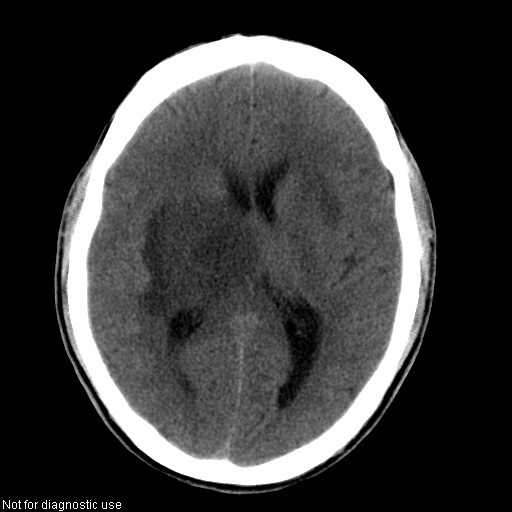

以下是引用hhcckk在2008-1-26 16:03:00的发言:[br]考虑病毒感染可能性大[br]1、病人发病时间短,1周,转移病灶时间长[br]2、楼主虽然没有告诉我们年龄,但从颅内情况来看,病人年纪不会很大,脑池,脑沟不是很明显,当然,可能有脑肿胀的原因,转移灶病人年纪一般较大[br]3、从病灶特点来看,转移多发生在灰白质交界区,多有指状水肿,占位效应明显,此病人呈对称性发布,发生在脑实质深部,与转移有所区别[br]4、病人经抗炎,止咳效果不好,可能是病毒感染,抗生素治疗效果不好[br]5、建议楼主1、增强 2、有呼吸系统的症状何不拍个胸片